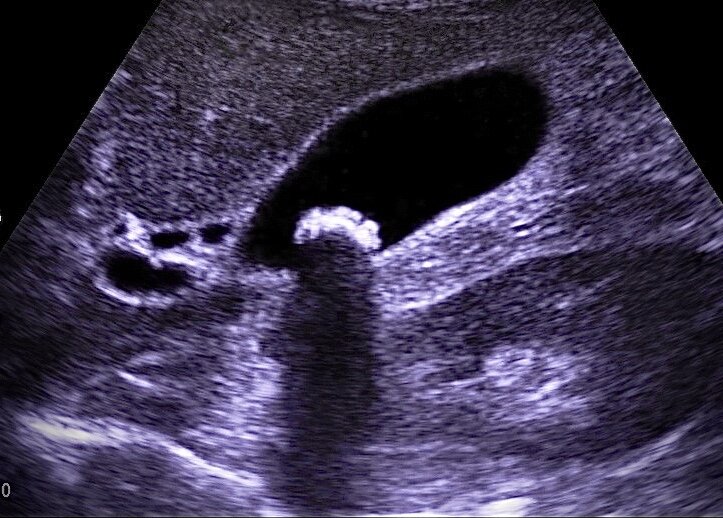

Нужно ли удалять желчный пузырь, если в нем образовались камни.

Одним из спорных вопросов в медицине является необходимость планового удаления желчного пузыря при желчнокаменной болезни. Желчнокаменная болезнь является довольно распространенным заболеванием, при котором камни в желчном пузыре или протоках обнаруживаются примерно у 10% населения, а в возрасте старше 70 лет - у 30% людей. Когда я училась еще в медицинском институте, преподаватели по общей хирурургии говорили, что при диагностировании желчнокаменной болезни необходимо проведение плановой лапароскопической холецистэктомии. Прошло уже более 15 лет с того момента и подходы к терапии камней в желчном пузыре несколько изменились. Согласно энциклопедии доказательной медицины UptoDate профилактическая холецистэктомия при желчнокаменной болезни не рекомендуется пациентам без каких-либо клинических симптомов. По статистике, при отсутствии жалоб (желтуха, боли в правом подреберье и др.) на фоне существующих камней в желчном пузыре, вероятность развития острого холецистита составляет около 1% в

По статистике, при отсутствии жалоб (желтуха, боли в правом подреберье и др.) на фоне существующих камней в желчном пузыре, вероятность развития острого холецистита составляет около 1% в год.

Поэтому при выявлении камней в желчном пузыре на УЗИ необходимо проконсультироваться с терапевтом или гастроэнтерологом и хирургом, которые смогут определить необходимую тактику лечения.